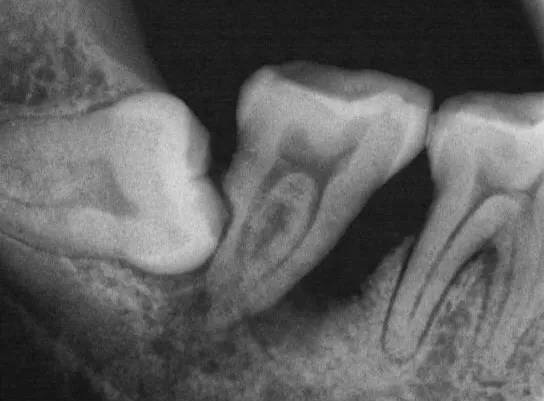

06.智齿造成邻牙病变

智齿萌发空间不足,常常会倒在第二磨牙上,因而造成第二磨牙清洁不易。智齿躺的时间一长,就会把旁边的邻牙都顶坏了,然后两颗都同归于尽。

这就是个玉石俱焚的案例。本来第一磨牙就缺失,智齿把第二磨牙也给顶牺牲了,种牙是在所难免了 | 作者供图